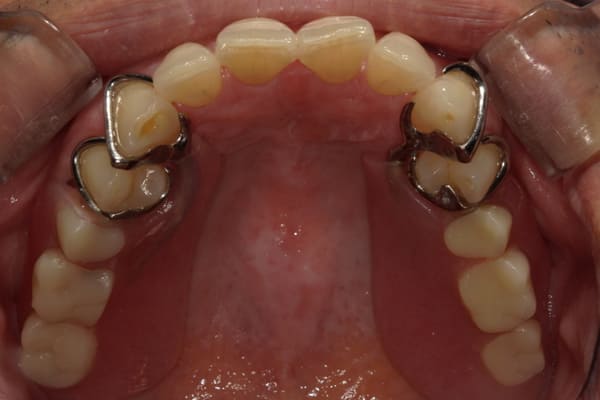

症例レポート[CASE.02]

入れ歯がカパカパして痛い、

歯がぐらぐらする

- 性別・年齢

- 男性(60代)

- 主訴

- 入れ歯がカパカパする、歯がぐらぐらして痛い、食いしばれない

- 治療

-

- 上顎精密総金属床総入れ歯

- 下顎精密金属床部分入れ歯

- ジルコニアクラウン4歯

- 治療期間

- 約3か月間

- 費用

- 上顎精密総金属床総入れ歯:55万円

- 下顎精密金属床部分入れ歯:55万円

(ミリング、ラベット加工込み) - ジルコニアクラウン:11万円×4歯

合計:154万円(税込)

上の前歯が重度歯周病により動揺し、残せない状態のため、入れ歯も動揺がありました。

ご自身の歯に負担の少ないバネ、また見た目も改善

バネをかける歯は繋げることで強度を増し、歯への負担を軽減し、歯の寿命を長くする設計へ。

バネがかかる歯の被せ物は、歯への負担を減らし、入れ歯が動きにくいようになる形態をあらかじめ付与することで、より入れ歯の機能が高まります。

治療を行う際、被せ物や入れ歯は、別々に考えるのではなく、一口腔単位としてお口全体のことを考え最良の治療計画を立てることが歯の寿命、機能効果を向上させるため、専門医としてこのことは常に心掛けて治療を行っています。

残りの歯に負担がかからないよう、被せ物と入れ歯の一体化を図った入れ歯

治療前は上下奥歯の入れ歯が削れていることで、かみ合わせが低くなり唇もつむった状態でした。

かみ合わせを適切な高さに戻したことで、本来の自然な口元へ。